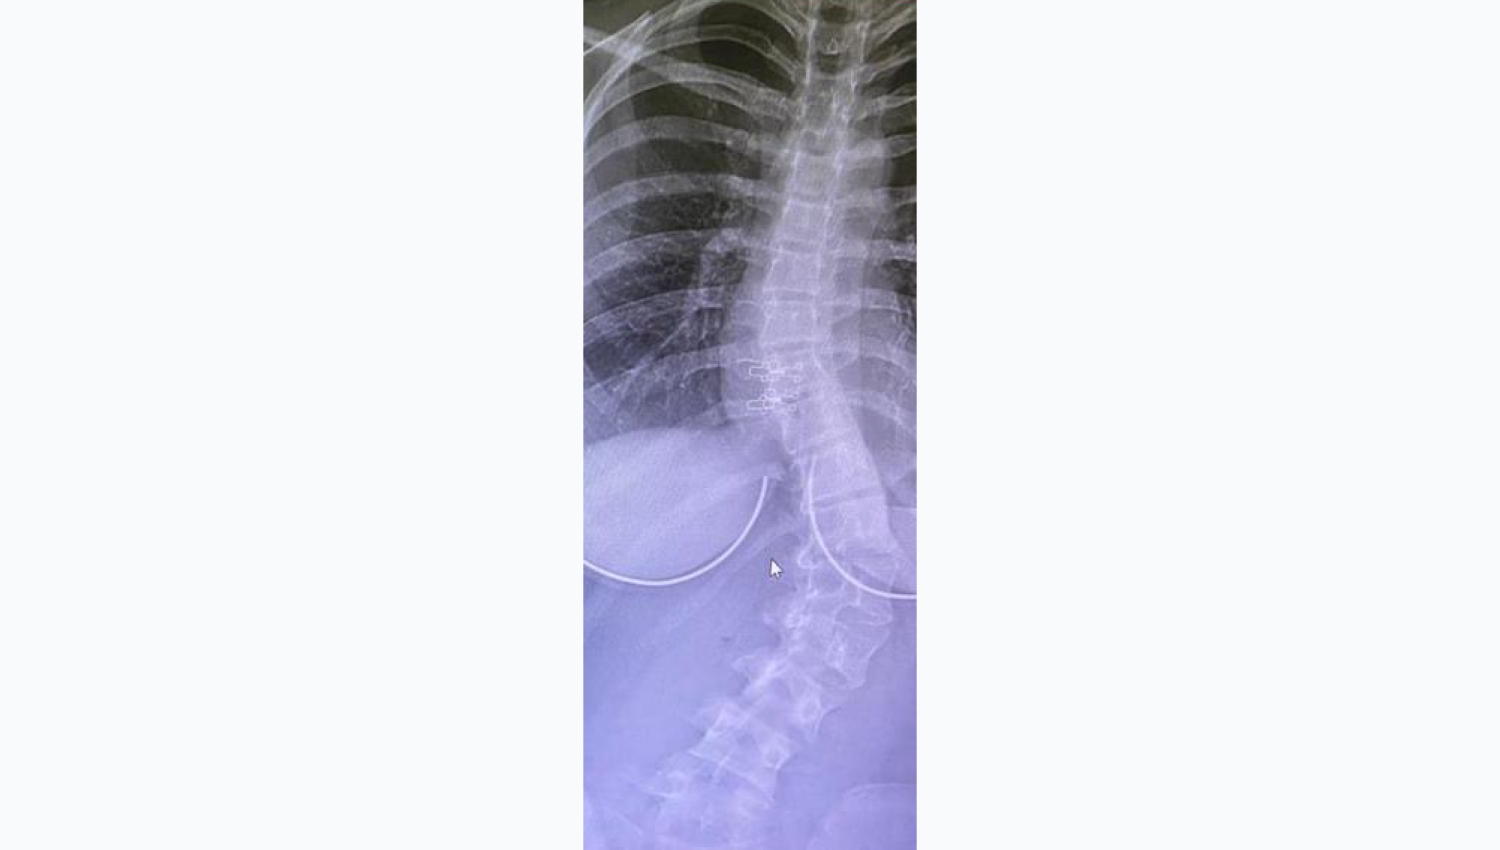

- Female, 16 years old.

- Powerbone Flexible Graft 60x62 was used

- during the operation of the patient whose

- diagnosis was Scoliosis.

- Case performed by Prof. Dr. Erol ÖKSÜZ

1.Initial radiological view.